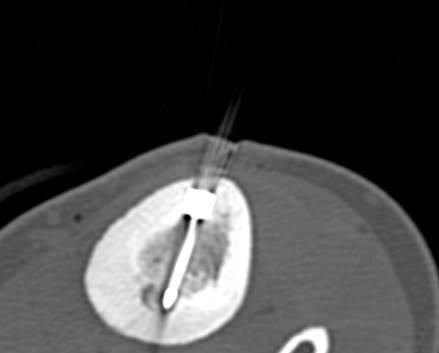

Abbildung: Bei der perkutanen Thermoablation von Lungentumoren werden spezielle Applikatoren unter CT-Bildgebung in den Zieltumor eingebracht. Durch Hitze wird der Tumor dann zerstört.